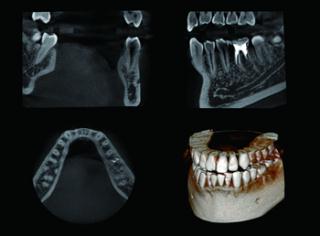

代田歯科医院は、2013年よりCTスキャン機能を備え、放射線量が少なく身体にも安全な最新のデジタル・レントゲンシステムを導入しています。

歯科用CTは、立体的なレントゲン画像を撮ることができ、放射線量も1/10と安心・安全な機械です。 またユニット前のモニターには、お待たせすることなくレントゲン画像が移され、口腔内カメラからの動画も見られます。

【

CT・デジタルレントゲン

】

CT画像